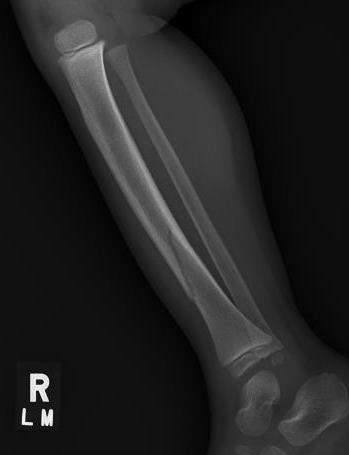

Undisplaced oblique fracture of distal tibia

- usually innocuous injury